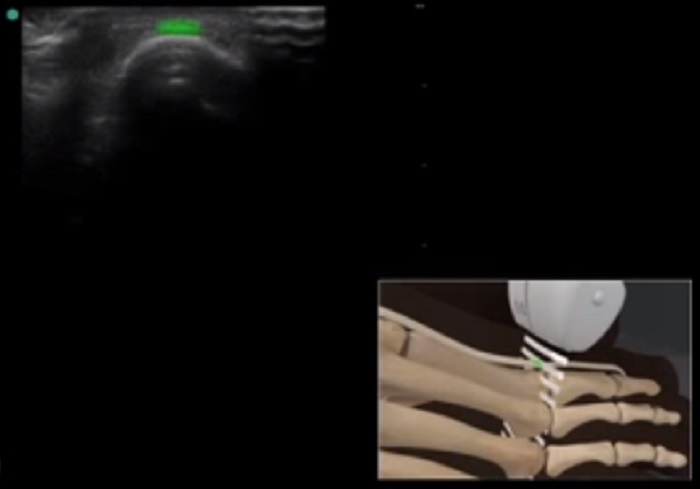

Foot & Ankle Extensor Tendon Transverse Image